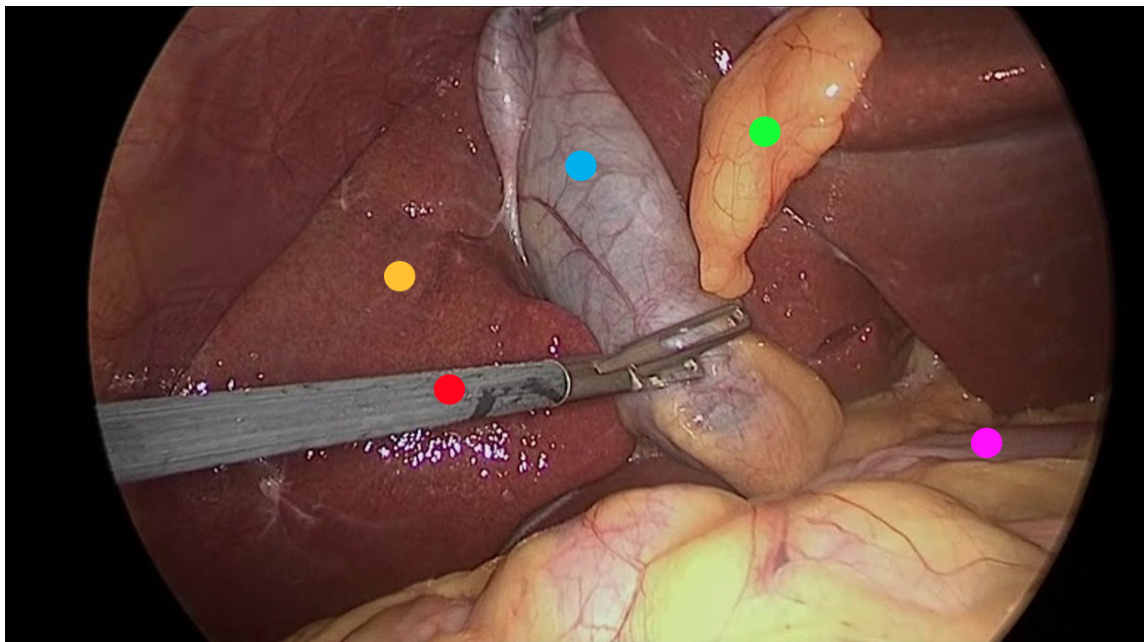

• Picture modal: Endoscopic picture • Tasks: La paros co pic c hole cyst ec to my • Reference Answer: – Yellow Dot: Liver. – Red Dot: Surgical grasper. – Blue Dot: Gallbladder. – Green Dot: Fats. – Purple Dot: Intestine.

• 图片模态:内窥镜图像

• 任务:腹腔镜胆囊切除术

• 参考答案:

- 黄点:肝脏。

- 红点:手术抓钳。

- 蓝点:胆囊。

- 绿点:脂肪组织。

- 紫点:肠道。

CASE 1 Control Group

In this chapter, we discovered that using color descriptors in scenarios where markers are also color-coded can significantly impair performance. In this showcase, the results were even worse than those in the control group (Section 4.5.1). Notably, all instances of yellow dots were incorrectly identified as fat. This misidentification likely stems from GPT-4V interpreting the yellow dots as part of the scene rather than as markers. When we described fat as "generally pale yellow," GPT-4V mistakenly classified the yellow dots as fat. This observation underscores the importance of careful consideration in using color descriptors, particularly in contexts where color plays a dual role in both the scene and the markers.

在本章中,我们发现当标记物也采用颜色编码时,使用颜色描述符会显著影响性能。本次展示的结果甚至比对照组更差(见第4.5.1节)。值得注意的是,所有黄色圆点都被错误识别为脂肪。这种误判可能源于GPT-4V将黄色圆点视为场景的一部分而非标记物。当我们描述脂肪为"通常呈淡黄色"时,GPT-4V错误地将黄色圆点归类为脂肪。这一发现凸显了在使用颜色描述符时需要格外谨慎,特别是在颜色同时承担场景元素和标记物双重功能的场景中。